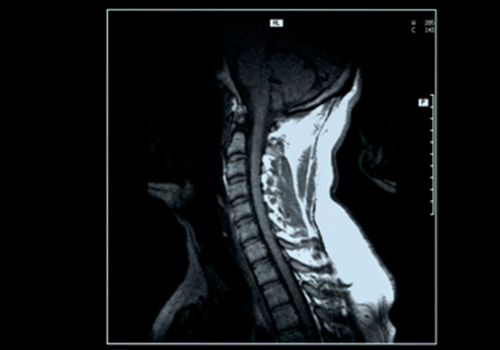

【参考】